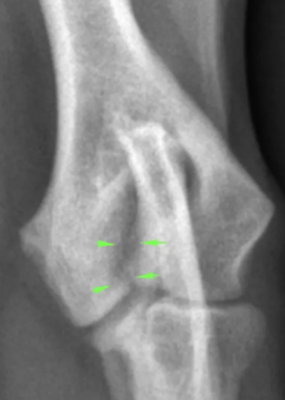

2. Radiographies du coude

Souvent le premier examen réalisé. Elles peuvent révéler :

- une fine ligne radiotransparente entre les condyles huméraux

- Une réaction périostée sur la crête épicondylaire latérale

- des signes d’arthrose précoce.

Plusieurs vues sont réalisées comprenant une face classique craniocaudal, une vue latérale en flexion, une vue oblique craniomédiale à caudolatérale avec une rotation de 15 degrés.

Cependant, la fissure peut être trop fine pour être visible.